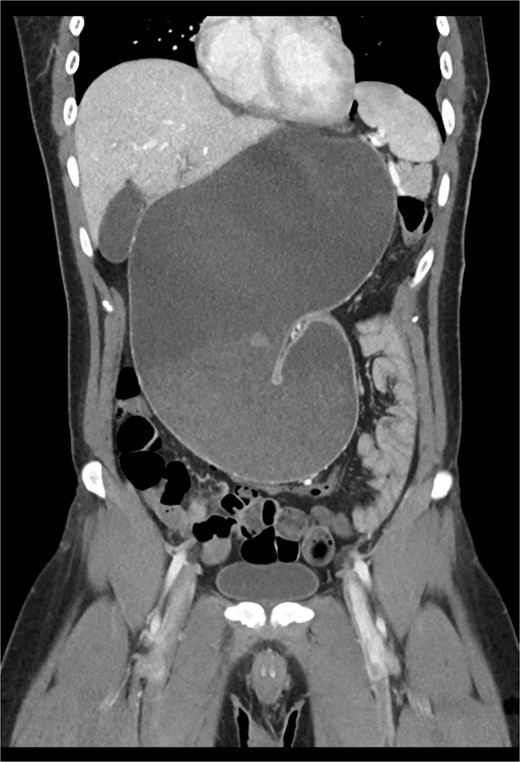

This is a case of a 26-year-old male patient who presented with symptoms of dyspnea on exertion, left chest pressure, and constipation for 7 years. He was a never smoker with no history of trauma, nor prior neck and chest surgeries. Baseline pulmonary functions tests revealed FEV1 of 71% predicted and DLCO of 77% predicted. Work-up included a computed tomography (CT) of the chest which revealed marked left hemidiaphragm elevation with compression atelectasis of the left lower lobe (Fig. 1). A fluoroscopic sniff test showed paradoxical movement of the left hemidiaphragm consistent with diaphragmatic paralysis. Interestingly, abdominal imaging obtained 14 months before surgery showed a displaced stomach but without volvulus (Fig. 2). Due to the impact on the patient’s quality of life, he was offered surgical treatment with a robotic-assisted left thoracoscopic plication of the diaphragm. This was done using a three-arm technique using the Da Vinci Xi surgical system (Intuitive Surgical, Sunnyvale, CA) with an additional assistant port. Plication was performed by placing multiple horizontal mattresses sutures reinforced with pledgets in an anterior–posterior orientation, and systematically working medial to lateral. A postoperative chest X-ray showed a satisfactory result (Fig. 3).

CT from 14-months pre-operation, demonstrating a full, but non-volvulized stomach.

The early postoperative course was unremarkable. The patient reported feeling mild bloating, but was discharged on postoperative Day 1 after removal of a chest tube (Fig. 4). A few hours after discharge from the hospital, he developed dysphagia, progressive abdominal pain, distension, and dyspnea that prompted a return to the hospital. Physical examination revealed tachycardia (132 bpm), mild hypoxia requiring supplemental O2 at 2 L/min via nasal canula, and abdominal distension. Laboratory studies showed WBC of 12 600 cells/μL. A CT scan of the abdomen and pelvis revealed a large, acute organo-axial gastric volvulus without evidence of ischemia, and an intact left hemidiaphragm plication at a similar height to the right hemidiaphragm (Fig. 5). A nasogastric tube was placed with immediate drainage of 1 L of dark bilious fluid with immediate relief of the patient’s symptoms. However, a subsequent film revealed the nasogastric tube projecting toward the upper left chest with presence of colonic haustra (Fig. 6), consistent with acute hemidiaphragm rupture.

CT revealing intact diaphragm plication with massive organo-axial gastric volvulus.